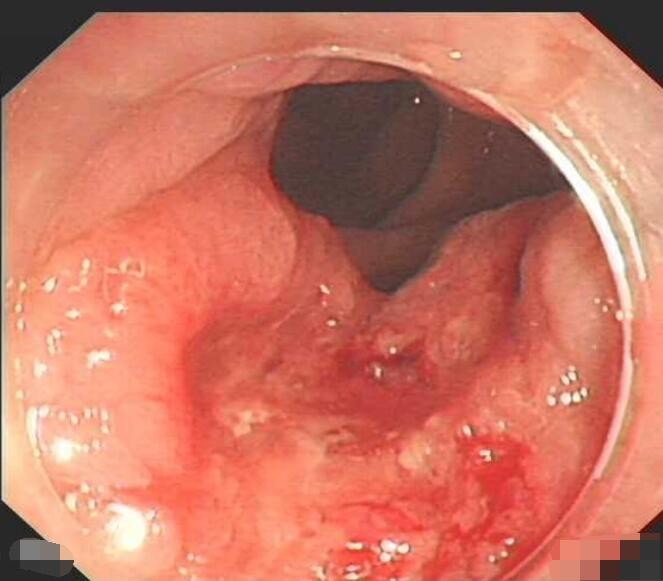

肛門癌圖片

肛癌早期症狀

A:肛門癌的病理類型以鱗狀上皮細胞癌為多見。肛門癌的病變多為突出皮面的結節樣的病變,觸摸時結節表面凹凸不平,多呈不規則形或者菜花樣,質地硬。結節的表面多有潰瘍性的改變,觸之易出血。結節與周圍組織分界不清楚,腫物的活動度差,常常難以推動。觸摸腫塊……